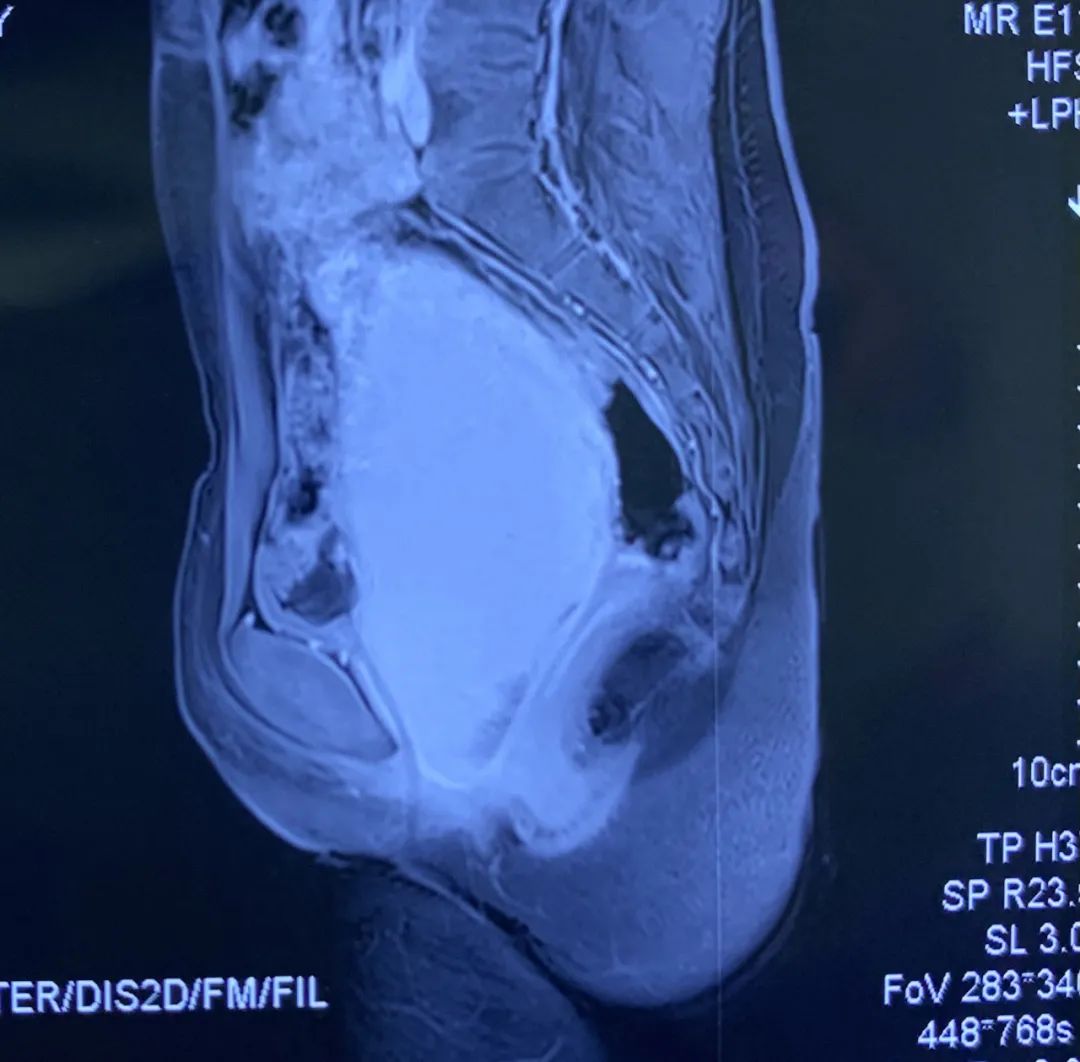

入院时,小月下腹部膨隆,腹痛难忍,接诊医师王江华仔细体检,当即给小月导出500ML尿液,缓解了小月的尿潴留及腹痛症状,并安排超声、MRI检查,进一步评估病情。检查提示小月的宫腔、宫颈及阴道内大量积液,进一步证实了处女膜闭锁。

此种情况需要尽快手术处理,解除闭锁的处女膜,引流经血,否则初潮后经血积存于阴道内,继之扩展到子宫,形成阴道子宫积血,积血过多可流入输卵管,通过伞部进入腹腔,伞部附近的腹膜受经血刺激发生水肿、黏连,致使输卵管伞部闭锁,形成阴道、子宫、输卵管积血、盆腔粘连,造成小月成年后的结婚及生育障碍。